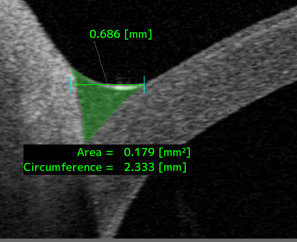

涙液メニスカス(下図右)の高さや面積を計測することにより、涙道疾患の術前後評価や涙液減少型ドライアイの評価に有用な情報を提供します。